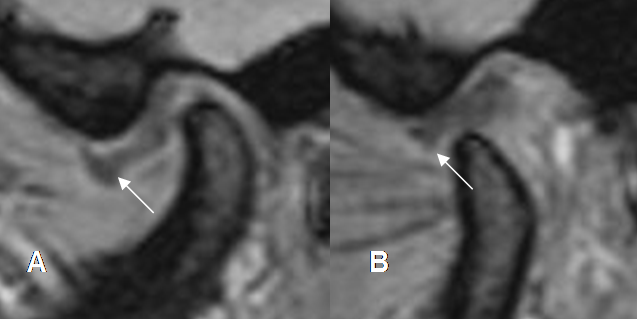

Fig 9. Disco luxado, que no reduce.

A: RM GE sagital oblicuo con boca cerrada. Disco con alteración de su morfología y señal, desplazado anteriormente.

B: RM GE sagital oblicuo con boca abierta. El disco persiste desplazado anteriormente.